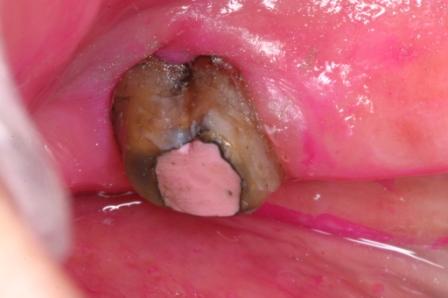

下顎7番の頬側歯茎部カリエスの原因 2025.06.04